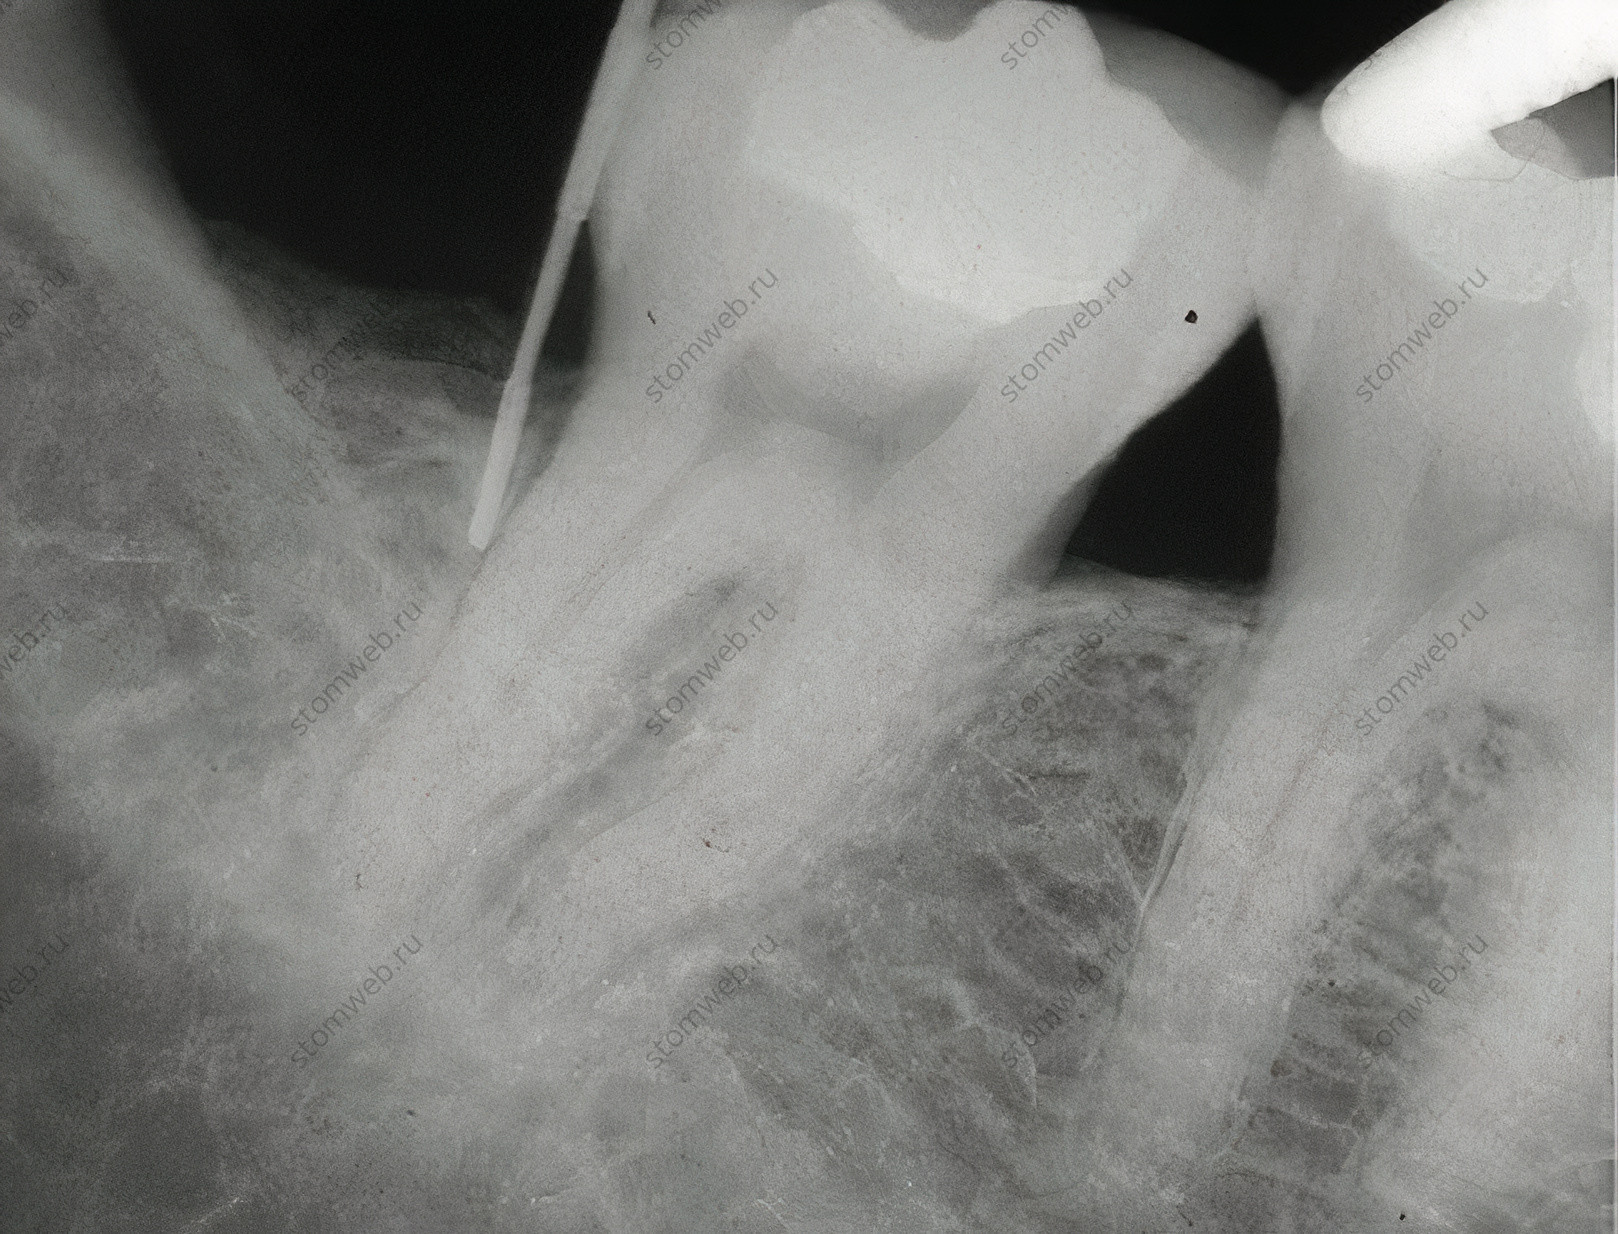

Вертикальные переломы чаще всего встречаются в эндодонтически пролеченных зубах (Рис. 2); случаи вертикальных переломов в витальных зубах были описаны, но встречались они у некоторых народов Азии со специфическими жевательными привычками. Вертикальные переломы в депульпированных зубах чаще всего появляются в апикальной части зуба и прогрессируют коронально; но иногда они появляются в пришеечной области и распространяются в длину. Диагноз обычно основывается на истории лечения (эндодонтическое лечение), рентгенологической картине и клинических проявлениях. В большинстве случаев зуб удаляется.

Рисунок 2. Рентгенограмма с показанным на ней верхнечелюстным первым премоляром с вертикальным переломом корня. Что характерно, такие переломы появляются в эндодонтически леченных зубах, и направление трещины обычно буккально-небное/язычное, хотя они и редко видны на снимках.